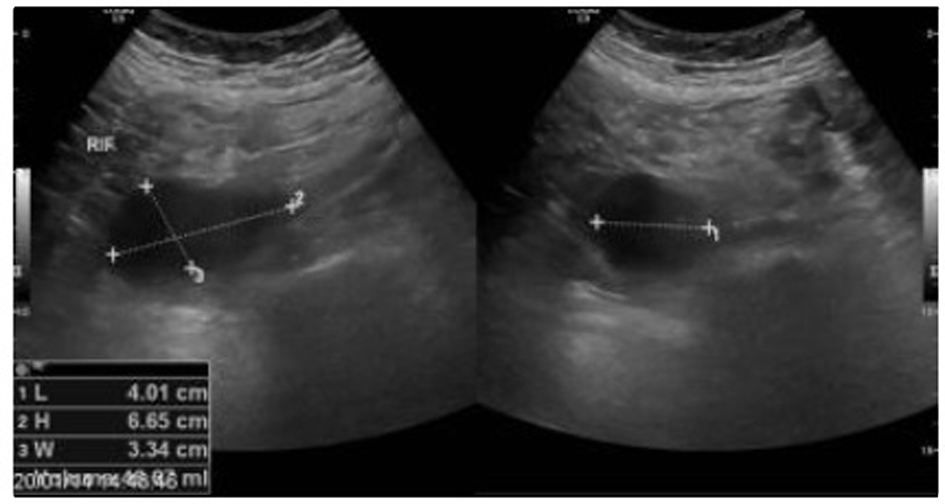

A 64-year-old man with prostate cancer, bone metastasis and coagulation disorder presented with abdominal distension. He underwent abdomen and pelvis ultrasound for assessment of ascitis, which showed localized fluid collections identified at the left iliac fossa with volume approximately 74 mL and right iliac fossa with volume approximately 48 mL (Fig. 1, 2).

![]() Click for large image | Figure 2. A localized fluid collection indentified at right iliac fossa with volume approximately 48 mL. |